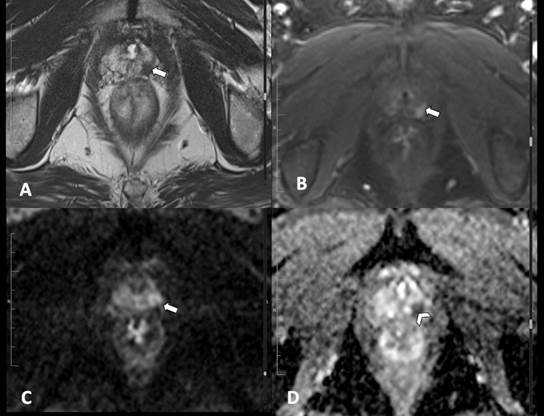

observador 3). Estos revisaron los estudios que cumplieron los criterios de inclusión (paciente con sospecha de carcinoma de próstata y RM con adecuados parámetros para su evaluación) mediante un visor de imágenes médicas (Hiruko, IMEXHS, Bogotá, Colombia). Calificaron las imágenes con los criterios principales del PI-RADS v. 2.1, consignaron los resultados en la herramienta de recolección descrita y emitieron una clasificación final para cada caso. En las Figs. 2, 3, 4, 5 y 6 se muestran ejemplos de las imágenes obtenidas y evaluadas según la clasificación PI-RADS v. 2.1.